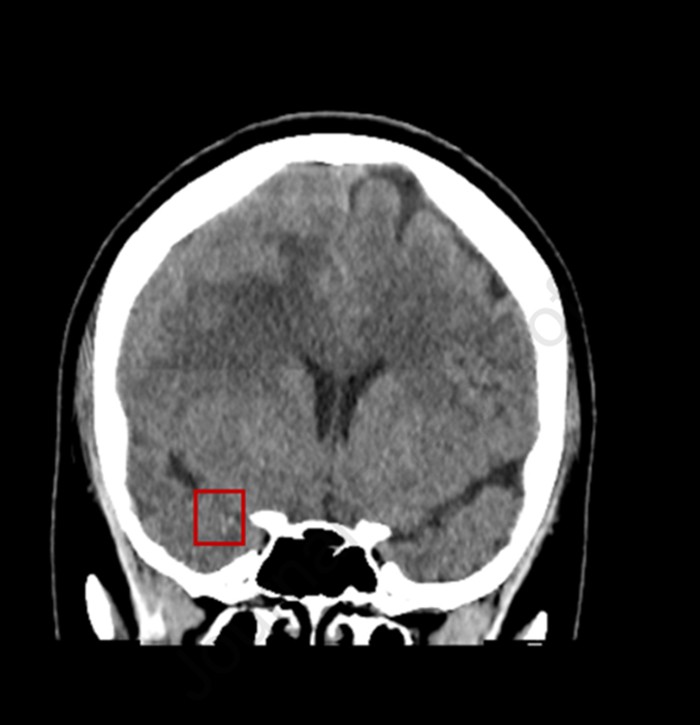

Shortly afterward, the patient developed expressive aphasia and left-sided weakness. Emergency imaging confirmed a right middle cerebral artery (MCA) infarction, with radiopaque material consistent with CaHA filler visible in the MCA (Figure 3). Given the proximity of the ICA to the intended injection site, the embolic event was attributed to inadvertent intravascular injection into the ICA. This case represents a severe form of calcium hydroxyapatite filler side effects, specifically a vascular complication.

Figure 3:Coronal reconstruction of a non-contrast head CT scan showing radiopaque calcium hydroxyapatite (CaHA) material within the middle cerebral artery (MCA, highlighted in red box), resulting in sequelae of acute infarction in the right cerebral hemisphere.